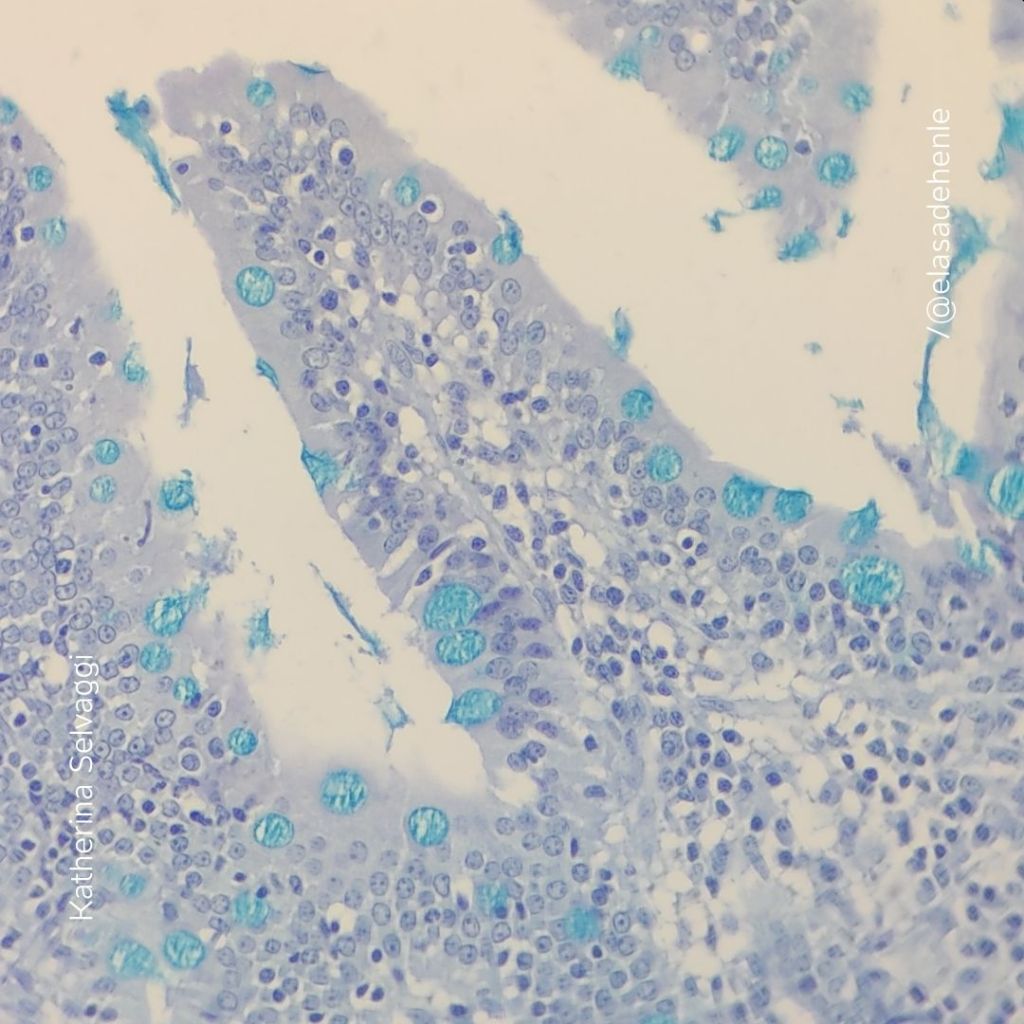

Alcian Blue

Intestino

EUTM